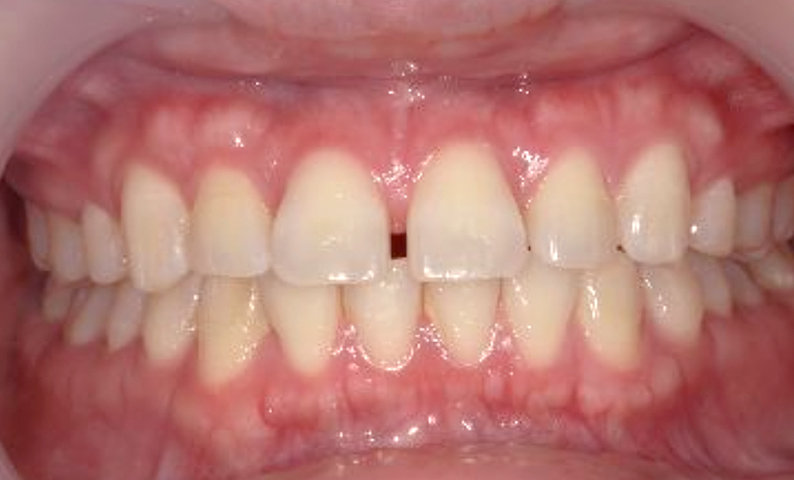

| 治療前 | 治療後 |

|---|---|

|